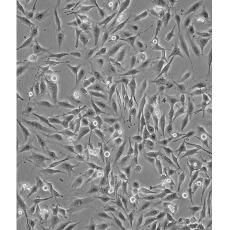

MDA-MB-435S

中文名稱 人乳腺導(dǎo)管癌細(xì)胞

組織來(lái)源 previously described as: mammary gland/breast; derived from metastatic site: pleural effusion

生長(zhǎng)特性 adherent

形態(tài)特征 spindle shaped

細(xì)胞描述 MDA-MB-435S是一種紡錘形的細(xì)胞,1976年由其親本(435)中篩選得到。435是從31歲的轉(zhuǎn)移性乳腺導(dǎo)管腺癌女性患者胸水中分離得到。當(dāng)用熒光染料對(duì)微管蛋白進(jìn)行染色時(shí)親本細(xì)胞顯現(xiàn)散布特征(II型)。最近通過(guò)cDNA陣列研究表明,親本(MDA-MB-435)可歸入黑素瘤起源。